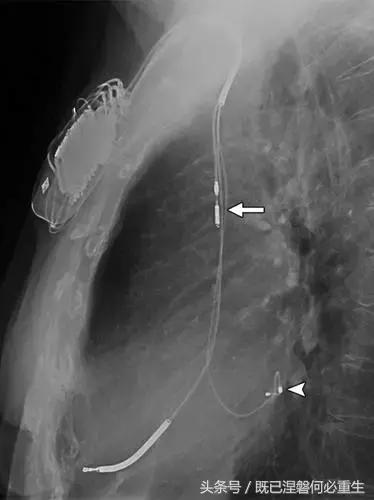

图。 7A 79岁的男性患有电极折断和迁移。

A,初始胸前X线片显示Pacesetter双腔起搏器低于锁骨的心房导线不完全断裂(变薄)(箭头)。

图。 7B 79岁的男性患有电极折断和迁移。

B,大约3年后,电极完全断裂,金属传导碎片(箭头)分离。 远端片段(箭头)已经偏移尾侧,但是由于围绕电极的射线可穿透鞘的约束效应而没有迁移到肺循环中。 引线和中心静脉导管最常见于锁骨和第一肋骨之间断裂,因为它们在臂运动期间被锁骨下肌肉或腱或肋锁韧带压缩[16]。

造成设备故障的最常见的X光检查原因之一是铅断裂。锁骨下静脉经过锁骨下的部位是骨折最常见的位置[16](图7A和7B)。在这个位置的损伤可能发生在导管或导线,并已被描述为锁骨下夹断综合征和锁骨下压溃综合征[16?18]。临床上,骨折的导线通常在患者中产生可以是连续的,间歇的或依赖于患者定位的症状。识别这些状况可能需要挑衅性的动作,例如等长臂锻炼,仰卧或侧向定位或Valsalva。设备检查将显示异常的起搏阻抗(如果绝缘破裂允许导体暴露则减小,如果导体断裂但绝缘完好则增加),感测错误和起搏捕获损失[12]。导线断裂或绝缘损坏可能导致感测或起搏异常。对心律失常的不适当的过感知或欠感应可能导致不适当的治疗,例如抗心动过速起搏和休克治疗,或不适当的抑制治疗。

用于将导线的近端部分固定到胸壁的导线固定件可以模拟损伤。扎带是通常位于锁骨和发生器之间并且可以压接引线的套囊(图8A和8B)。熟悉这种外观和通常的射线透射束缚的位置可以防止错误报告磨损的线索。